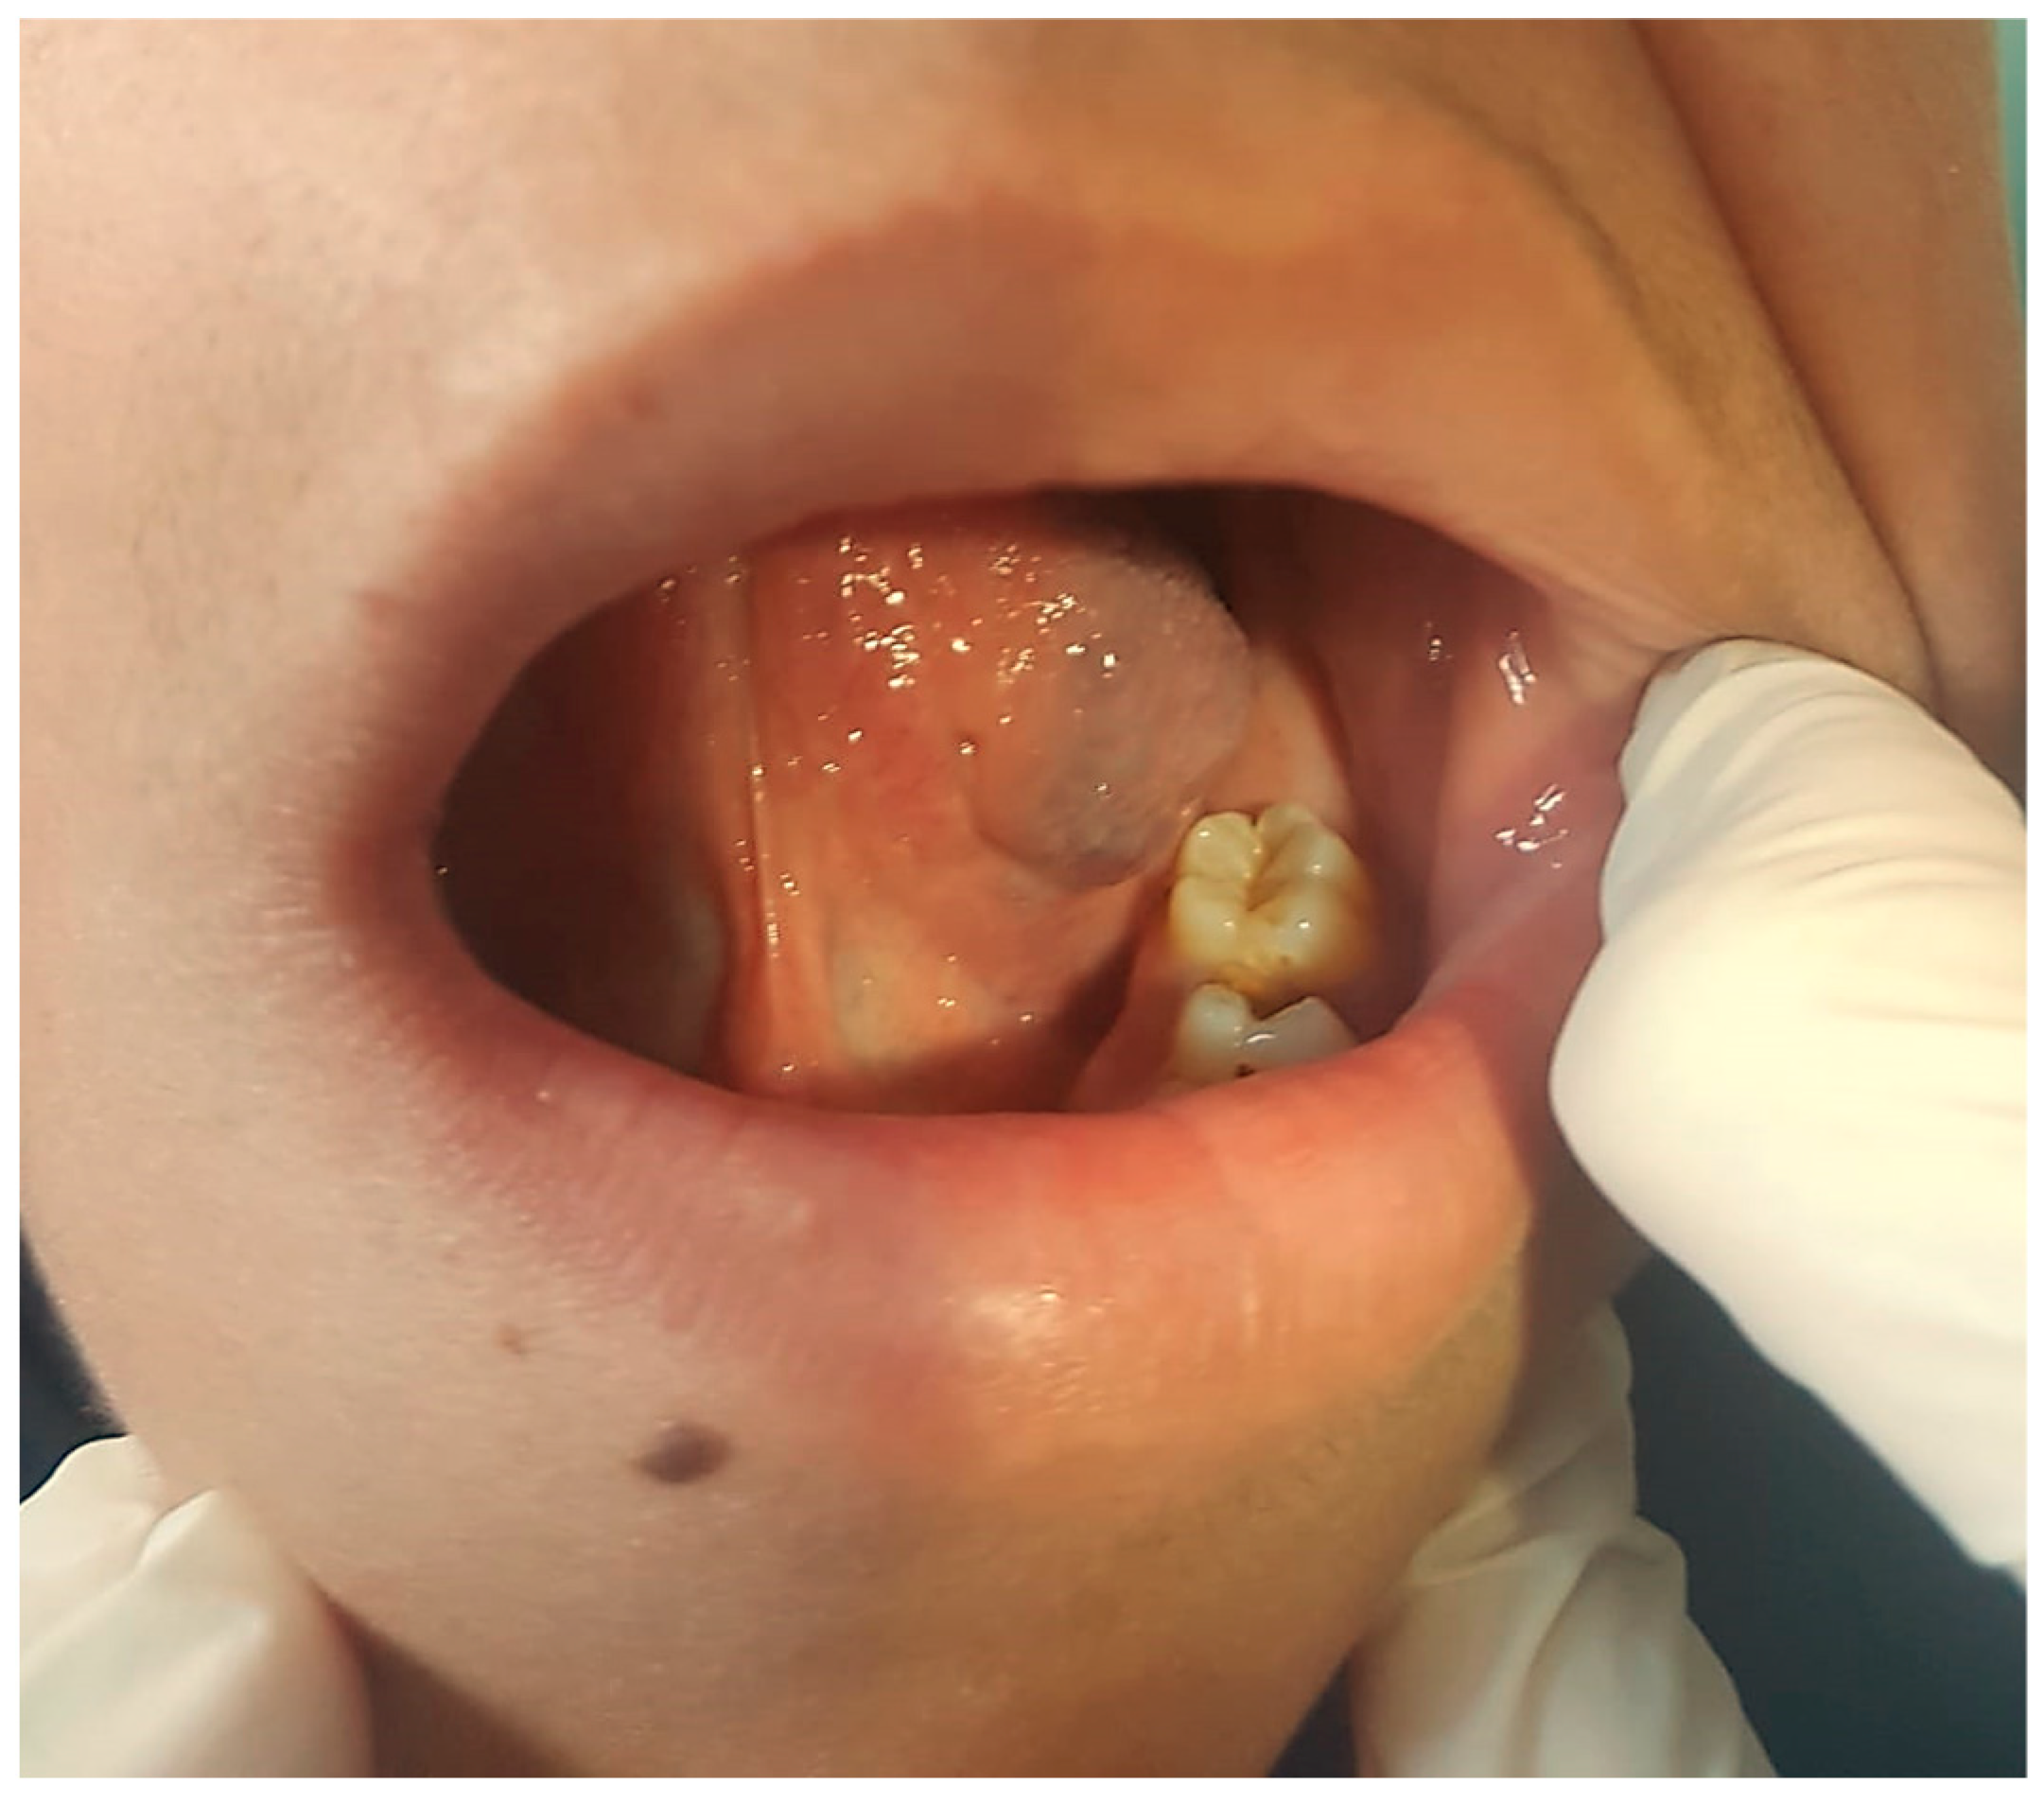

3.1. Venous Malformations

3.1.1. Clinical Data

3.1.2. Diagnosis

3.1.3. Therapy

3.2. Lymphatic Malformations

3.2.1. Clinical Data

3.2.2. Diagnosis

3.2.3. Therapy